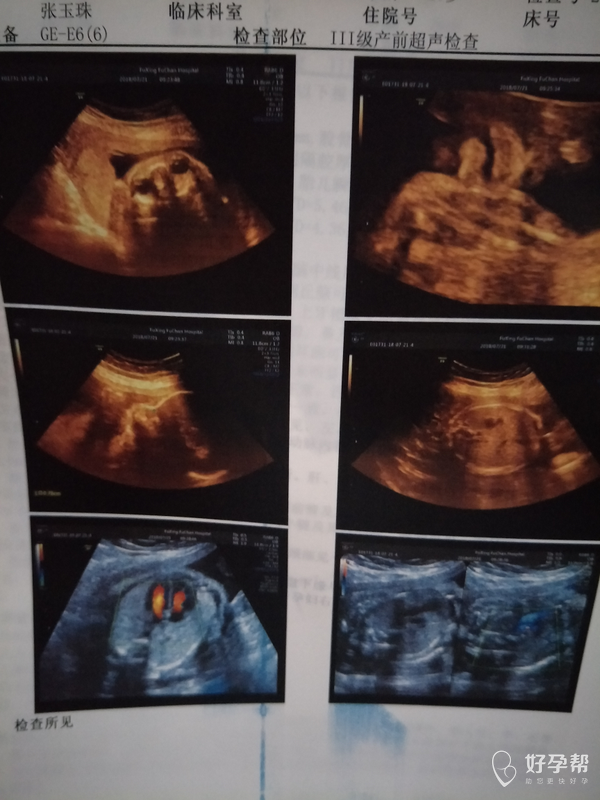

好害怕麻烦医生帮忙看看有没有事